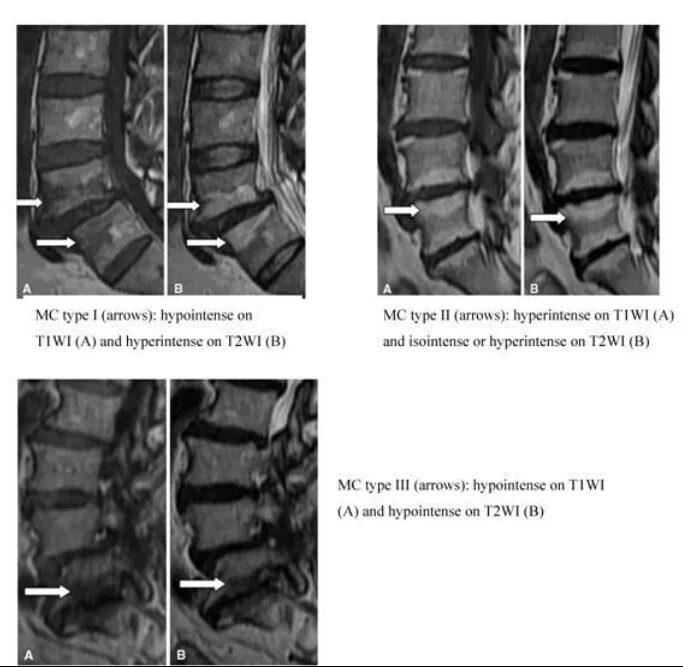

Modic тип 1